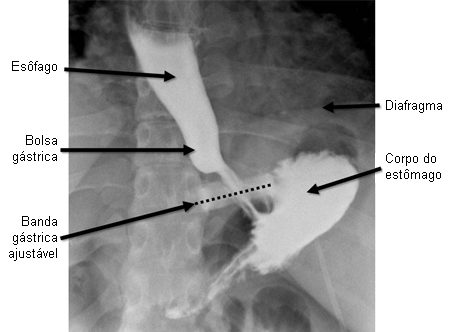

A banda gástrica é uma das operações bariátricas menos realizadas. A reoperação relacionada a dispositivo é comum e cara.[91] Os desfechos de longo prazo sugerem resultados de perda de peso inferiores aos observados no bypass ou gastrectomia vertical.[92] Vários dispositivos de banda gástrica ajustáveis (AGB) são aprovados pela Food and Drug Administration dos EUA.Geralmente são colocadas ao redor do corpo do estômago, logo distal à junção gastroesofágica, e agem restringindo o volume gástrico.[Figure caption and citation for the preceding image starts]: Banda gástrica ajustável por via laparoscópicaCopyright ©2008 Daniel M. Herron, MD; usada com permissão [Citation ends].

A grande maioria das cirurgias de BGA são realizadas por abordagem laparoscópica. Em geral, a cirurgia por via aberta é usada somente quando as considerações técnicas impedem a abordagem laparoscópica. Tipicamente, 5 a 6 incisões, cada uma com 5 mm a 15 mm, são usadas para o acesso laparoscópico. Uma incisão é aumentada para permitir a colocação da porta de acesso na parede abdominal. A BGA é colocada ao redor da parte superior do estômago, logo abaixo da junção gastroesofágica. A parte interna da banda inclui um balão toroidal que pode ser inflado com solução salina, injetada pela porta de acesso subcutânea. A capacidade para a solução salina varia de 4 mL a 15 mL, dependendo do dispositivo. A injeção de solução salina na porta aperta a banda, e a remoção de solução salina afrouxa a banda. Em geral, o cirurgião bariátrico aperta as bandas o suficiente para resultar na restrição de ingestão, mas não tão apertado para causar vômitos, desconforto ou alargamento esofágico (pseudoacalásia). A capacidade de solução salina varia de 4 mL a 15 mL. A porta de acesso é geralmente bem visível na radiografia abdominal simples e pode ser palpada no exame do abdome. Em radiografias, a banda geralmente parece estar com 20-40 graus de rotação em relação ao horizontal, com a lateral esquerda maior que a direita. Bandas com angulação diferente podem ter escorregado de sua posição normal.

Após a colocação da banda, o estômago permanece acessível à endoscopia alta, embora possa ser necessário remover antes parcialmente ou totalmente o fluido da banda.[Figure caption and citation for the preceding image starts]: Radiografia de trato gastrointestinal superior em pacientes com banda gástrica ajustável na posição normal. A linha tracejada está sobreposta na banda para enfatizar a angulação normal, com a lateral esquerda angulada para cima em aproximadamente 20-40 graus em relação ao horizontal. Observe a bolsa bem pequena entre a banda e o diafragmaDo acervo de Daniel M. Herron, MD [Citation ends].

O deslizamento da banda, que pode causar prolapso gástrico, pode ocorrer em 5% dos pacientes ou mais.[93] As radiografias abdominais simples mostram um ângulo da banda normal de aproximadamente 20 a 40 graus em relação ao horizontal, com a lateral esquerda maior que a direita. Bandas com angulação diferente podem ter escorregado de sua posição normal. Uma banda orientada verticalmente sugere deslizamento com prolapso do estômago posterior através da banda, enquanto uma banda orientada horizontalmente sugere um deslizamento anterior. O escorregamento da banda geralmente resulta em obstrução parcial ou completa do estômago associada a dor abdominal. O esvaziamento da banda pode aliviar os sintomas. Os sintomas persistentes após o esvaziamento podem indicar comprometimento vascular do estômago, necessitando de revisão cirúrgica urgente ou remoção da banda.